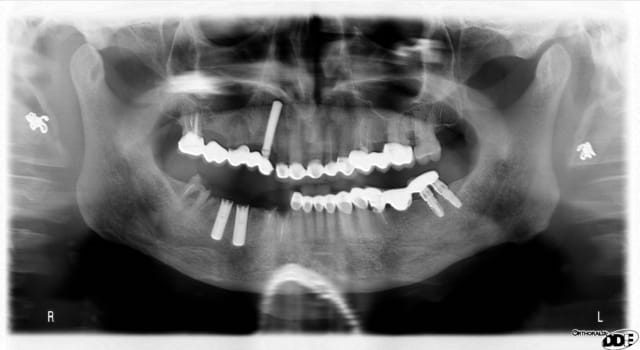

la patiente a des implants artisanaux posés une vingtaine d'années plus tôt... mais qui tiennent bon

dans un 1er temps (fevrier 09) extraction de 15 greffe et pose de 2 implants en position de 14 et 16 (soulevé crestal)

mi juin 09 contrôle et pose du bridge sur implants

mi mars 2010 (+ 9 mois) contrôle pas ou très peu de perte osseuse

Pour le cas de sinclair qui est tres interressant tu nous montres les radios de tes 2 implants 14 16 qui me semble etre des astra qui sont bien posé avec un choix de vis sans pb mais tu ne nous montres pas le même raisonnement avec les autres implants notamment l implant en 44 ou 45 (je suis désolé je n ai plus la radio en face de moi)qui semble présenter un elargissement au niveau du col implantaire. aurais tu une explication? alors que les implants ancestraux sont semble t il stable meme si comme le montre ta premiere pano les vis de transfixation se sont cassées. en revanche excellente idée de faire un inlay core en lieu et place des piliers implantaires.